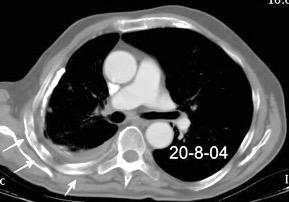

En el hemotórax, los elementos formes de la sangre tienden a depositarse en la parte más declive

Polireddy K et al. Blunt thoracic trauma: role of chest radiography and comparison with CT findings and literature review . Emerg Radiol 2022.

Neumo-Hemotórax

Sin fracturas: 6,7%

1-2 fracturas: 24,9% + de 3 fracturas:81,4%

Colección pleural

Hemorrágica.30-70 UH

Extravasación iv con sangrado activo.>90 UH “Simpático”..<15 UH